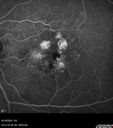

77 year old female HPI: CC: Decreased Vision OU. Since Last Visit: worsening. Location: central vision. Context nset/Aggravation: while reading. Modifying Factors: when closes one of her eyes notices letters are missing. Duration of Problem: couple of months. Associated Symptoms: foggy circle temporal when driving OU. Severity: moderate. Course: intermittent . HPI obtained by Steven M. Cohen, MD, FACS Medical Hx: Hypertension, Systemic. Hyperlipidemia. Depression. Spinal Stenosis. Psoriasis. Osteopenia Systemic Meds: TIZANIDINE HCL. TRAMADOL HCL prn. ZOLPIDEM. HYDROCORTISONE. TRAZODONE HCL, Clobex 0.05 % Topical Spray. VA OD 20/32, OS 20/20 IOP 13 OU